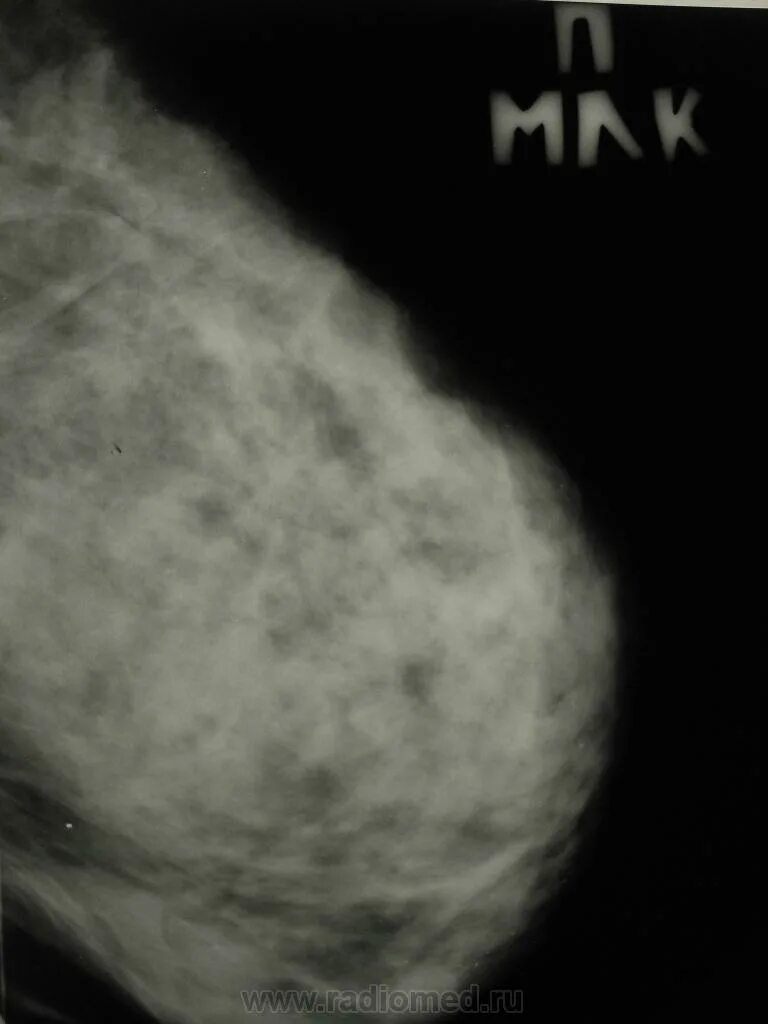

Склерозирующий аденоз молочных желез